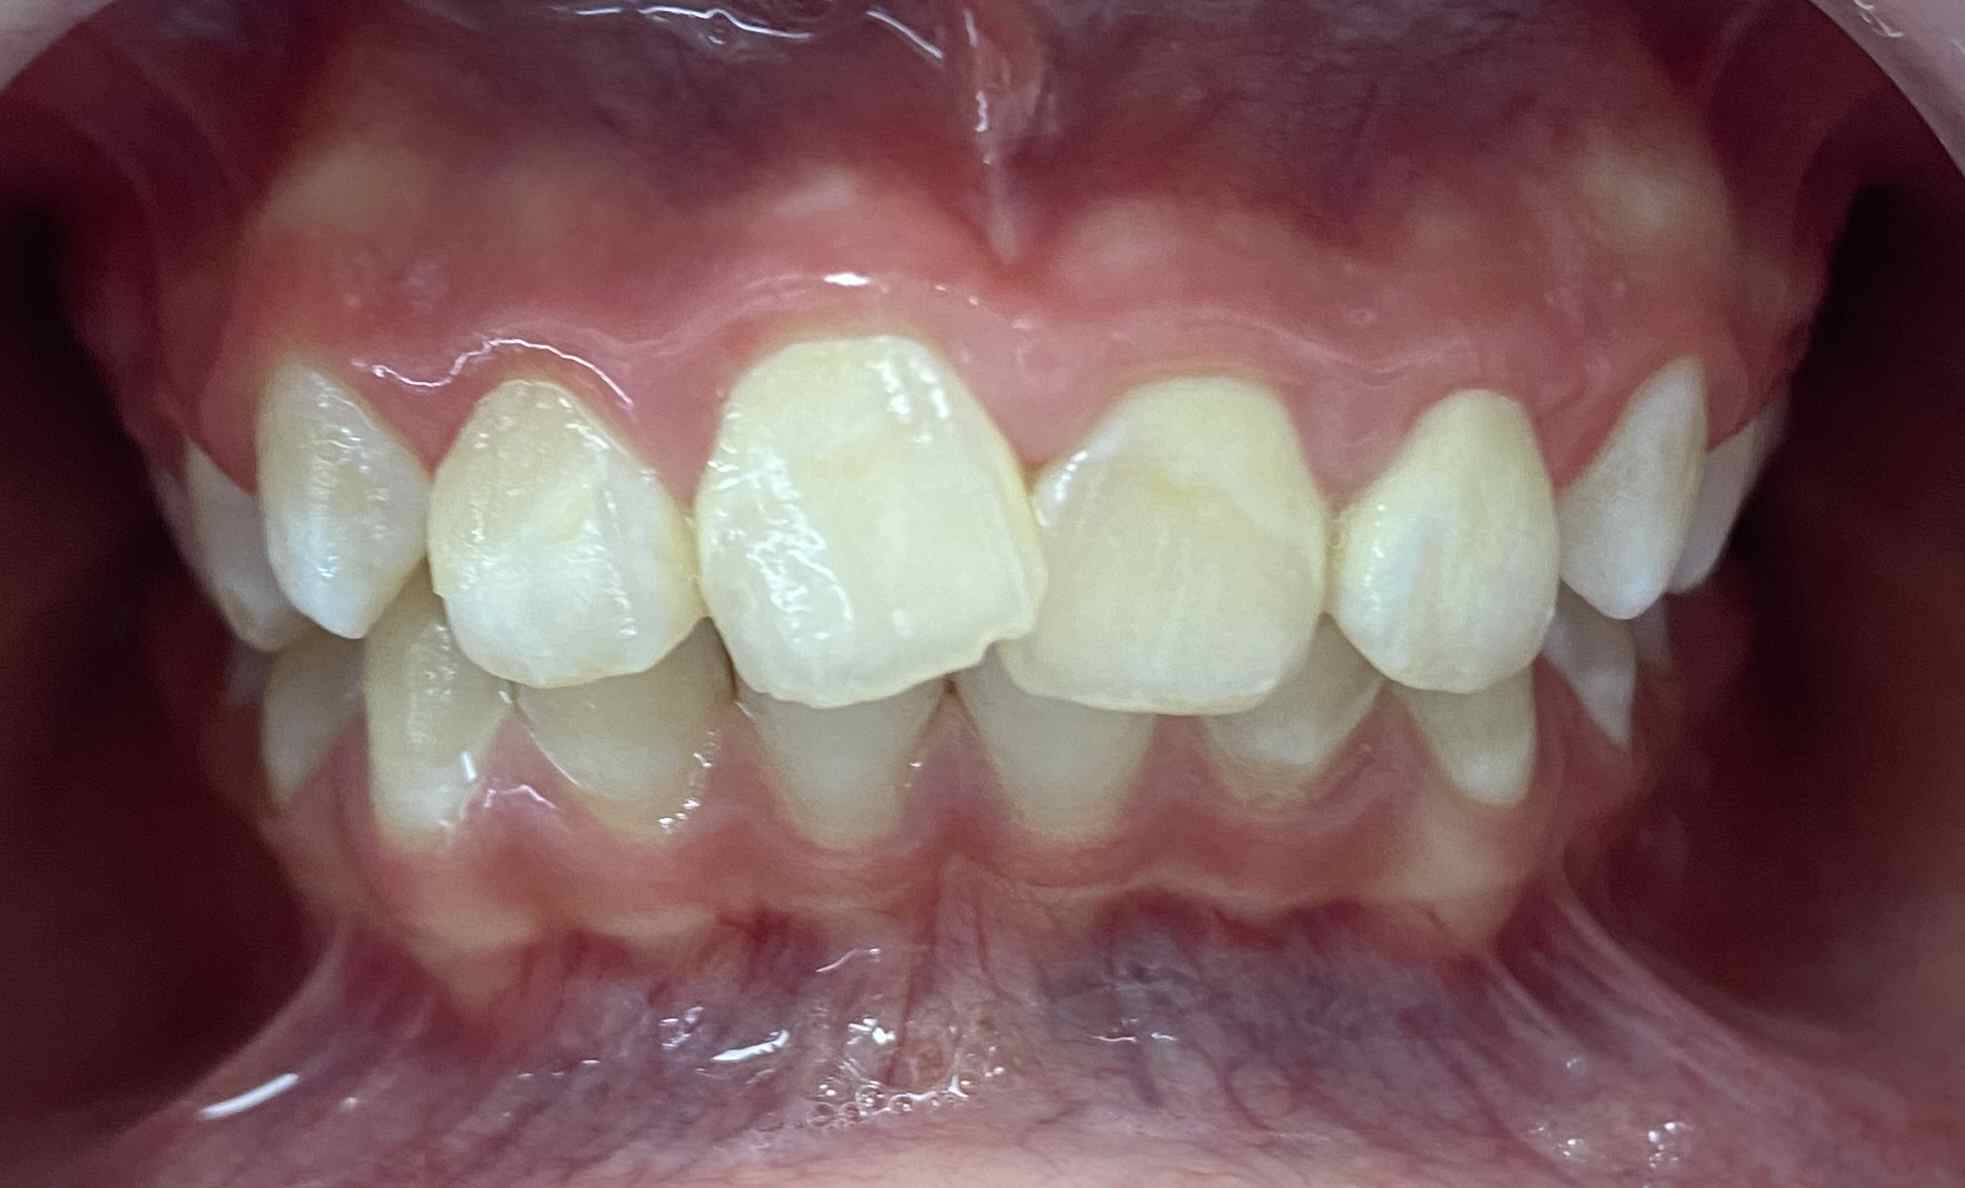

Pic.16. Mesial position of tooth 11 with lack of space in the dental arch.